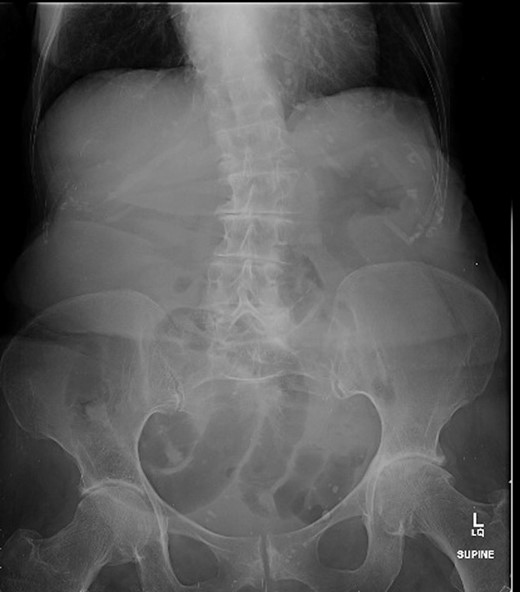

A 88-year-old woman presented to the ED with abdominal pain, vomiting, right hip pain and diarrhoea. Medical co-morbidities include ischaemic heart disease, hypertension and bilateral osteoarthritis of the hip. Her surgical history includes three Caesarean sections, open cholecystectomy, umbilical hernia repair and left mastectomy for breast cancer. A computed tomography (CT) abdomen revealed small bowel obstruction due to the right OH (Fig. 1) and evidence of a small left OH. A trial of conservative management was made for patient due to her age, multiple co-morbidities and patient's wishes. Bowel obstruction resolved with conservative management. The patient re-presented 1 month later with small bowel obstruction and pain radiating down medial left leg. There were no clinical signs of intestinal ischaemia. Abdominal x-ray was consistent with small bowel obstruction (Fig. 2) and CT abdomen revealed transition point at left OH (Fig. 3). A decision was made to proceed with midline laparotomy and bilateral OH repair. Intra-operatively, there was a large right OH containing a small bowel, which was reduced, and a bard polypropylene mesh plug inserted into the defect and fixed with prolene interrupted sutures. The left OH was smaller and was repaired primarily with prolene. The patient made an unremarkable recovery, and she was discharged 3 days after the operation. No recurrence was noted within a year of follow-up.

(a and b) Small bowel obstruction secondary to a right OH. (a) Coronal and (b) axial.